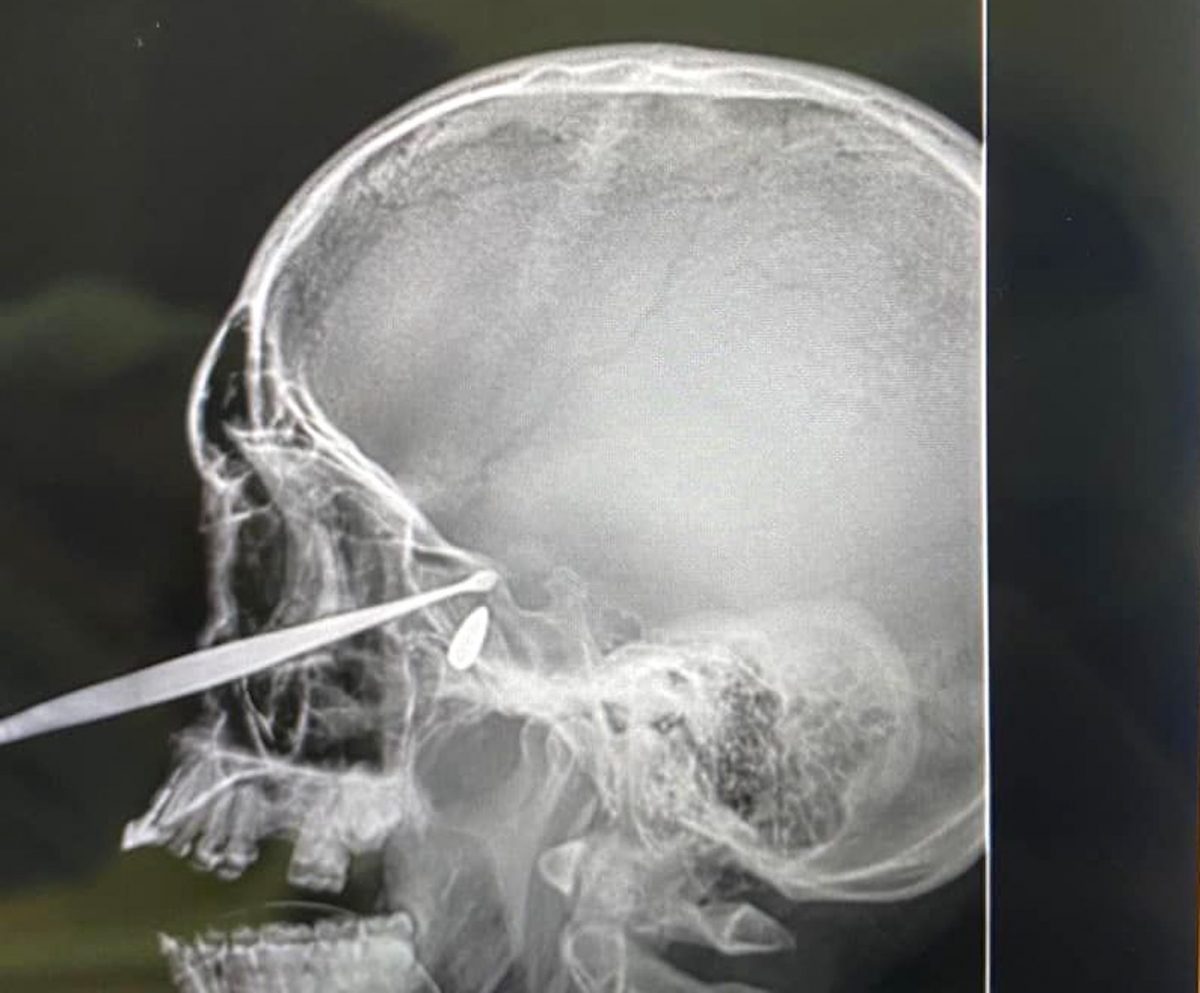

Днями до Дніпропетровської обласної клінічної лікарні імені І. І. Мечникова доправили військовослужбовця Збройних Сил України, який дістав важке кульове поранення в голову на одній із ділянок бойових дій. Він перебував між життям та смертю, проте завдяки професіоналізму та ювелірній роботі медиків воїн вижив.

Про цю неймовірну історію рятування українського захисника повідомив лікар-отоларинголог, кандидат медичних наук Анатолій Бакаєв.

— Ворожа куля зупинилась під основою черепа, — розповів Анатолій Анатолійович. — Завідувач відділення отоларингології № 1 лікарні Мечникова, заслужений лікар України Ярослав Соколенко та завідувач кафедри отоларингології Дніпровського державного медичного університету, професор, доктор медичних наук Олександр Ковтуненко провели операцію — виконали ендоназальне ендоскопічне видалення кулі з-під основи черепа.

Операція рятування воїна була проведена з допомогою найкращого світового медичного обладнання.

— Нині пацієнт швидко одужує, з гарним настроєм і дуже вдячний мечниківцям за свій рятунок, — розповів лікар Анатолій Бакаєв.